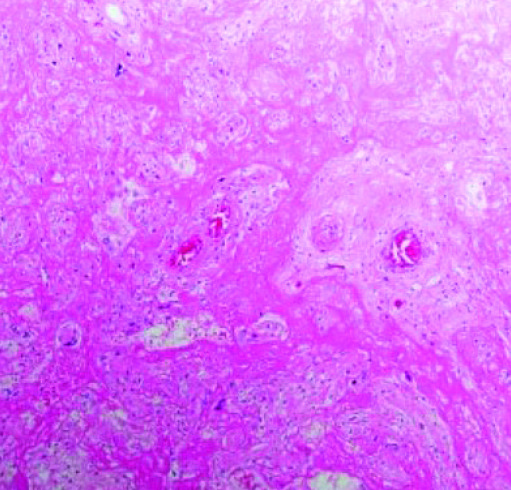

Рисунок 3. Массивное выпадение фибрина.Массивное выпадение фибрина (см. рис. 3) — очень заметный и яркий признак. Иногда ворсины настолько замурованы выпавшим фибрином, что их трудно найти и рассмотреть, циркуляция материнской крови нарушена. Газообмен в плаценте значительно снижается или вовсе прекращается, что ведет к гипоксии и гибели плода.

Рисунки 6, 7. Лимфогистиоцитарный виллит, тромбоз.Лимфогистиоцитарный виллит, тромбоз (см. рис. 6, 7).

В межворсинчатом пространстве видны скопления воспалительного инфильтрата, тромбоз сосудов ворсин, нарушения созревания ворсинчатого хориона.

«Стереотипная реакция плаценты на повреждение — это нарушение созревания. Как по литературным данным, так и на собственном опыте мы с этим сталкивались при подтвержденном COVID-19. В отличие от зрелой плацентарной ткани видна очень рыхлая строма. При выраженном лимфогистиоцитарном виллите, как правило, наблюдается тромбоз сосудов — и крупных, и капилляров».

Сканируя гистологические препараты на малом увеличении, мы видели крупные участки тромбоза с массивным выпадением фибрина в межворсинчатом пространстве. На большом увеличении в периферии участков тромбоза наблюдается воспалительная инфильтрация в ворсинах и межворсинчатом пространстве. Можно рассмотреть, как фибрин буквально заклеивает собой ворсины.

В основном это свежий фибрин, хотя наблюдаются и участки более зрелого фибрина. То есть на морфологическом уровне мы предполагаем, что поражение плаценты происходит достаточно быстро и ведет к гибели плода. Все это подтверждается и клиническими данными.